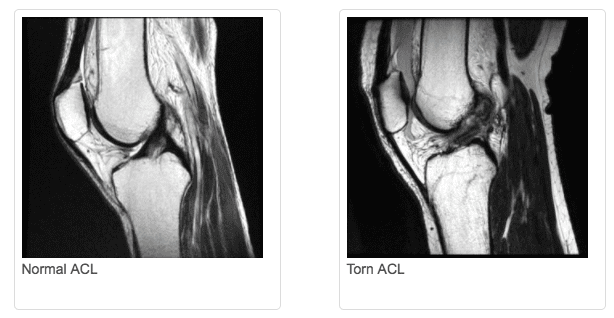

The ACL (anterior cruciate ligament) is one of the most commonly injured ligaments of the knee (ACL Tear). The ACL provides support for lateral movements and quick bursts of speed. The risk of an ACL injury is higher in people who participate in high-risk/high-speed sports like football, soccer, basketball, rugby, and skiing.

Many athletes eventually undergo ACL tear surgery to reconstruct the torn ACL, but treatment should be individualized based on each person’s activity level and goals.

To see pictures of a torn ACL, including before-and-after pictures of ACL reconstruction surgery, please visit our knee arthroscopy gallery.